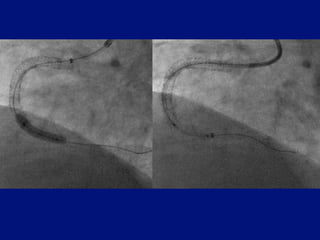

Balloon / stent delivery CTO

CCI in press 2010 Mamas Ordoubadi Fraser

More difficult stent delivery

Extension crosses tortuousity

easier than stent

Pull catheter in over balloon inflated

distal lesion

Pulling is less traumatic than pushing

Wire re-centered

Conventional anchor